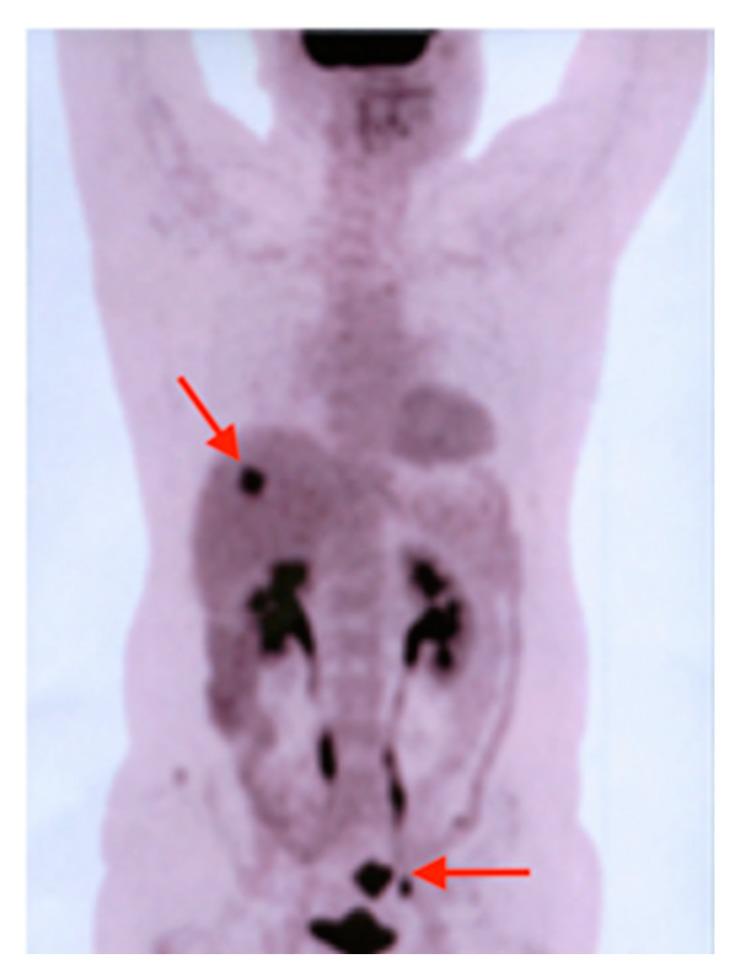

Multiple primary malignant tumors are defined by the development of more than one malignancy in a single patient. These can be subdivided into synchronous or metachronous malignant tumors, depending on their time of appearance, relative to the first malignancy. Triple primary malignancies are a relatively rare occurrence in day-to-day practice and triple synchronous or metachronous carcinomas involving a thyroid localization are even less common. In this case series, we report our 20-year experience in diagnosing and managing five patients with triple malignant tumors with thyroid involvement.

多原发性恶性肿瘤是指在单个患者中发生一种以上恶性肿瘤。根据它们相对于首次发生的恶性肿瘤的出现时间,可将其细分为同时性或异时性恶性肿瘤。三原发性恶性肿瘤在日常实践中相对少见,而涉及甲状腺定位的三发性同时性或异时性癌则更为罕见。在本病例系列中,我们报告了我们在诊断和管理5例伴有甲状腺受累的三发性恶性肿瘤患者方面的20年经验。